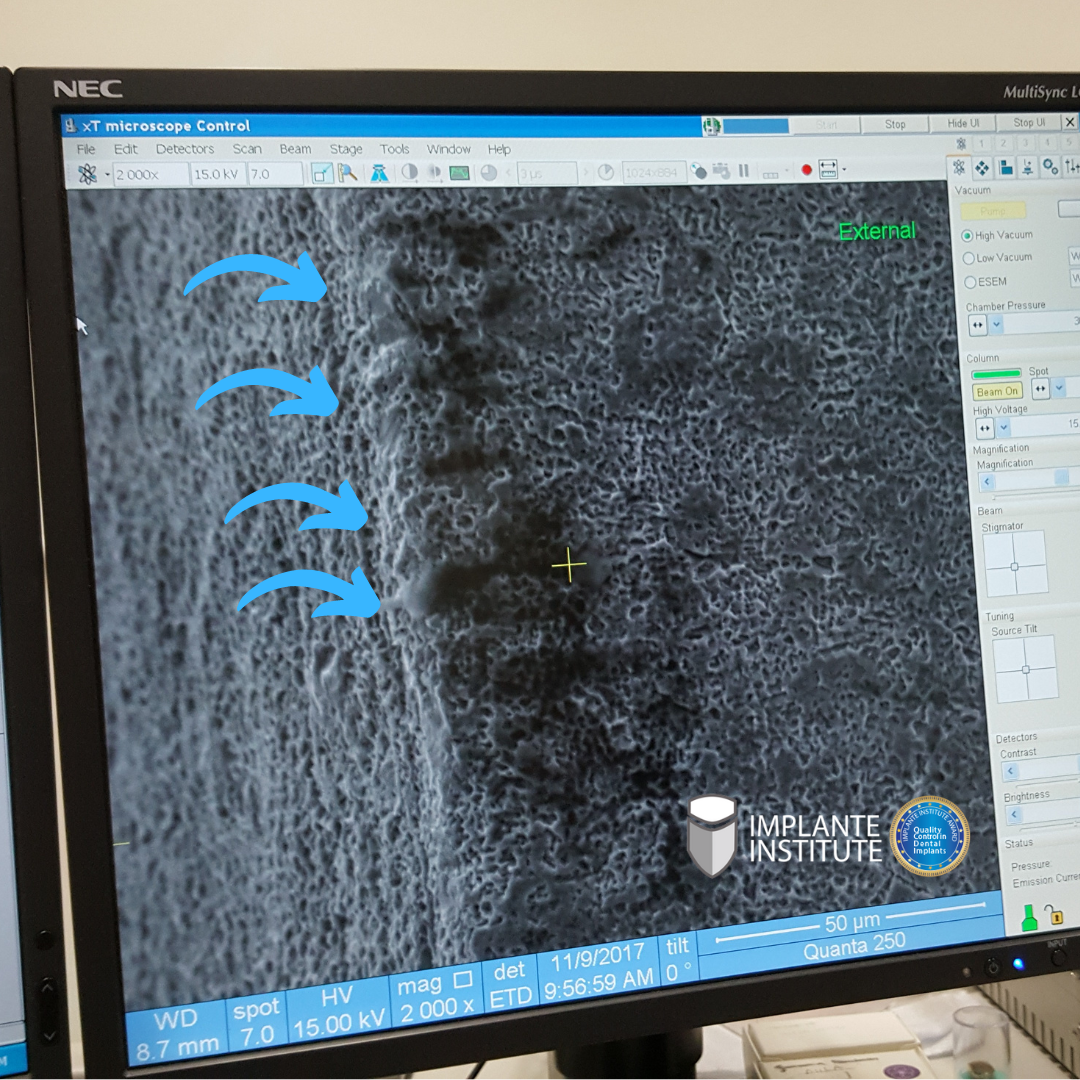

Look at this analysis, notice that something scraped and deposited on the implant surface.

Whoever said it was the plastic in the packaging was right.

The softer material (plastic) when it rubs against the harder material with a rough surface (implant) deposits it, and thus contaminates it.

Microplastics are plastic particles measuring millimeters and nanometers.

Microplastics are a significant concern as they can pose a threat after entering human bone and bloodstream through contaminated implants.